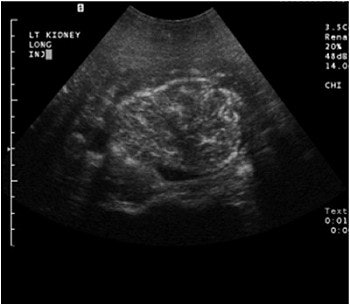

![]() |

A complex cystic mass with a solid portion slightly higher in echogenicity in the cystic component, pre-contrast (above) and post-contrast administration (below). The echogenic component is markedly enhanced on contrast and is a cystic renal carcinoma. Images courtesy of Dr. Richard Barr, Ph.D.